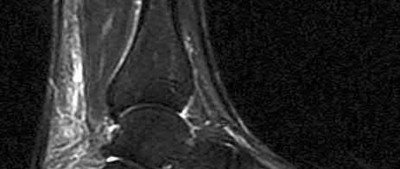

4. # After undergoing the treatment seen in Figure A, when should a patient be expected to safely operate the brakes of an automobile?

Corrent answer: 4

Figure A shows a patient after an open reduction and internal fixation of a bimalleolar ankle fracture.

Egol et al showed that by nine weeks, the total braking time of patients who had undergone fixation of a displaced right ankle fracture returns to the normal, baseline value.

Egol et al, also found that appropriate braking time returns at a point 6 weeks after initiation of weightbearing after treatment of lower extremity long bone and periarticular fractures, as examined with a driving simulator. No differences were seen in return of braking time between periarticular fractures and long bone injuries.